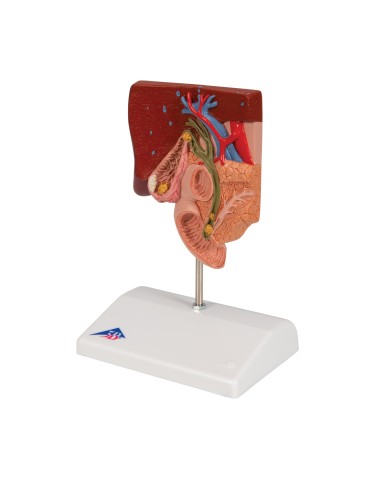

I Modelli anatomici 3B scientific ed Erler Zimmer sono quanto di meglio esista per studiare l'anatomia del corpo umano, il catalogo dei modelli anatomici comprende modelli di cranio, scomponibili, colorati, crani anatomici, crani su cavalletto, e il modello di punta, il cranio in 22 parti, ad incastro magnetico.

Questo e tanto altro ancora trovi nella sezione dedicata ai modellini anatomici, occhi, denti, orecchio, naso e gola, e i modelli anatomici per ostetricia e ginecologia, per lo studio dell'anatomia della pelvi e del bacino umano.

I modelli anatomici didattici sono riproduzioni di strutture anatomiche perfettamente uguali a quelle vere, i modelli di ossa sono realizzati dalla scansione di ossa vere, l'esperienza tattile è assolutamente realistica, ed anche il peso delle ossa corrisponde all'incirca al peso delle ossa vere.

Sono indispensabili per lo studio dell'anatomia umana, oggi è possibile osservare le strutture anatomiche senza la necessità di dissezionare cadaveri o di effettuare studi pericolosi su pazienti vivi.

Gli studenti di medicina utilizzano i modelli anatomici per i loro studi di anatomia umana, studiare l'anatomia sui libri non basta, un modellino anatomico permette uno studio molto più accurato che una foto o un disegno su un libro.

Medici, fisioterapisti, osteopati e professionisti sanitari utilizzano i modelli anatomici per dare spiegazioni ai pazienti sulle patologie, risparmiando tanto tempo prezioso durante la spiegazione, che diventa molto più efficace.